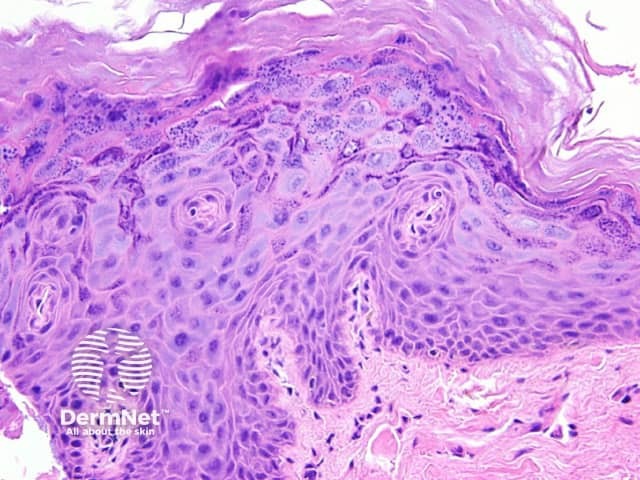

Histopathology of EV lesions shows enlarged cells in the granular or spinous layer. These have a quite distinctive blue-gray swollen cytoplasm. (figure 1) which reflects HPV infection by the unusual HPV types seen in this disorder. There may be enlarged keratohyaline granules and koilocytes.

Figure 1

Squamous cell carcinoma in situ (Bowen disease) — sometimes the cytoplasm in a non-HPV induced dysplastic epithelium can be pale or clear similar to that seen in figure 1. EV lesions may also harbour dysplasia or carcinoma.